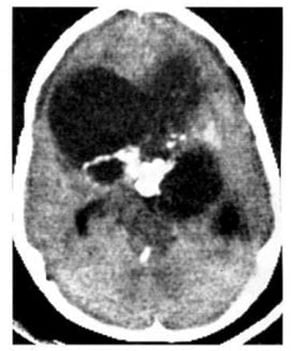

Hình 1.43. Khối máu tụ tươi trong não ở một trẻ nhỏ. Máu có mật độ cao trong bán cầu não bên phải, phù mật độ thấp bao quanh. Tụ dịch mãn dưới màng cứng hai bên. Đây là một trường hợp trẻ bị bạc đãi.